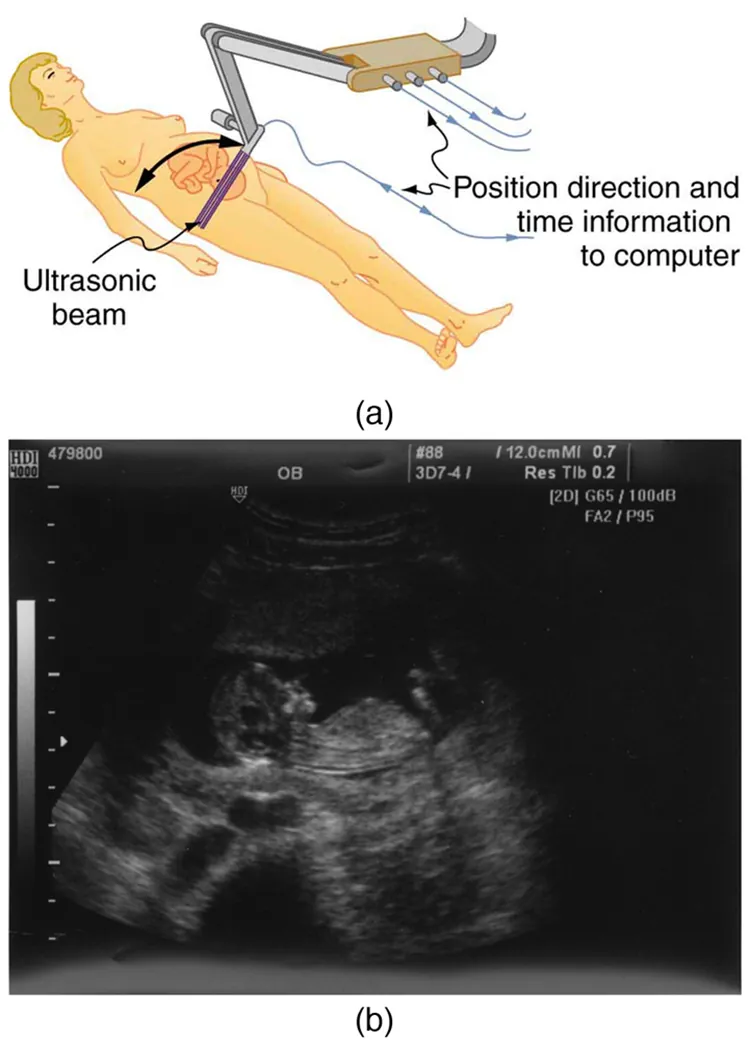

The most common ultrasound applications produce an image like that shown in Figure 17.47. The speaker-microphone broadcasts a directional beam, sweeping the beam across the area of interest. This is accomplished by having multiple ultrasound sources in the probe’s head, which are phased to interfere constructively in a given, adjustable direction. Echoes are measured as a function of position as well as depth. A computer constructs an image that reveals the shape and density of internal structures.

The first part of the diagram shows an ultrasound device scanning a woman’s abdomen. The second part of the diagram is an ultrasound scan report of the abdomen.

Figure 17.47 (a) An ultrasonic image is produced by sweeping the ultrasonic beam across the area of interest, in this case the woman’s abdomen. Data are recorded and analyzed in a computer, providing a two-dimensional image. (b) Ultrasound image of 12-week-old fetus. (credit: Margaret W. Carruthers, Flickr)

How much detail can ultrasound reveal? The image in Figure 17.47 is typical of low-cost systems, but that in Figure 17.48 shows the remarkable detail possible with more advanced systems, including 3D imaging. Ultrasound today is commonly used in prenatal care. Such imaging can be used to see if the fetus is developing at a normal rate, and help in the determination of serious problems early in the pregnancy. Ultrasound is also in wide use to image the chambers of the heart and the flow of blood within the beating heart, using the Doppler effect (echocardiology).